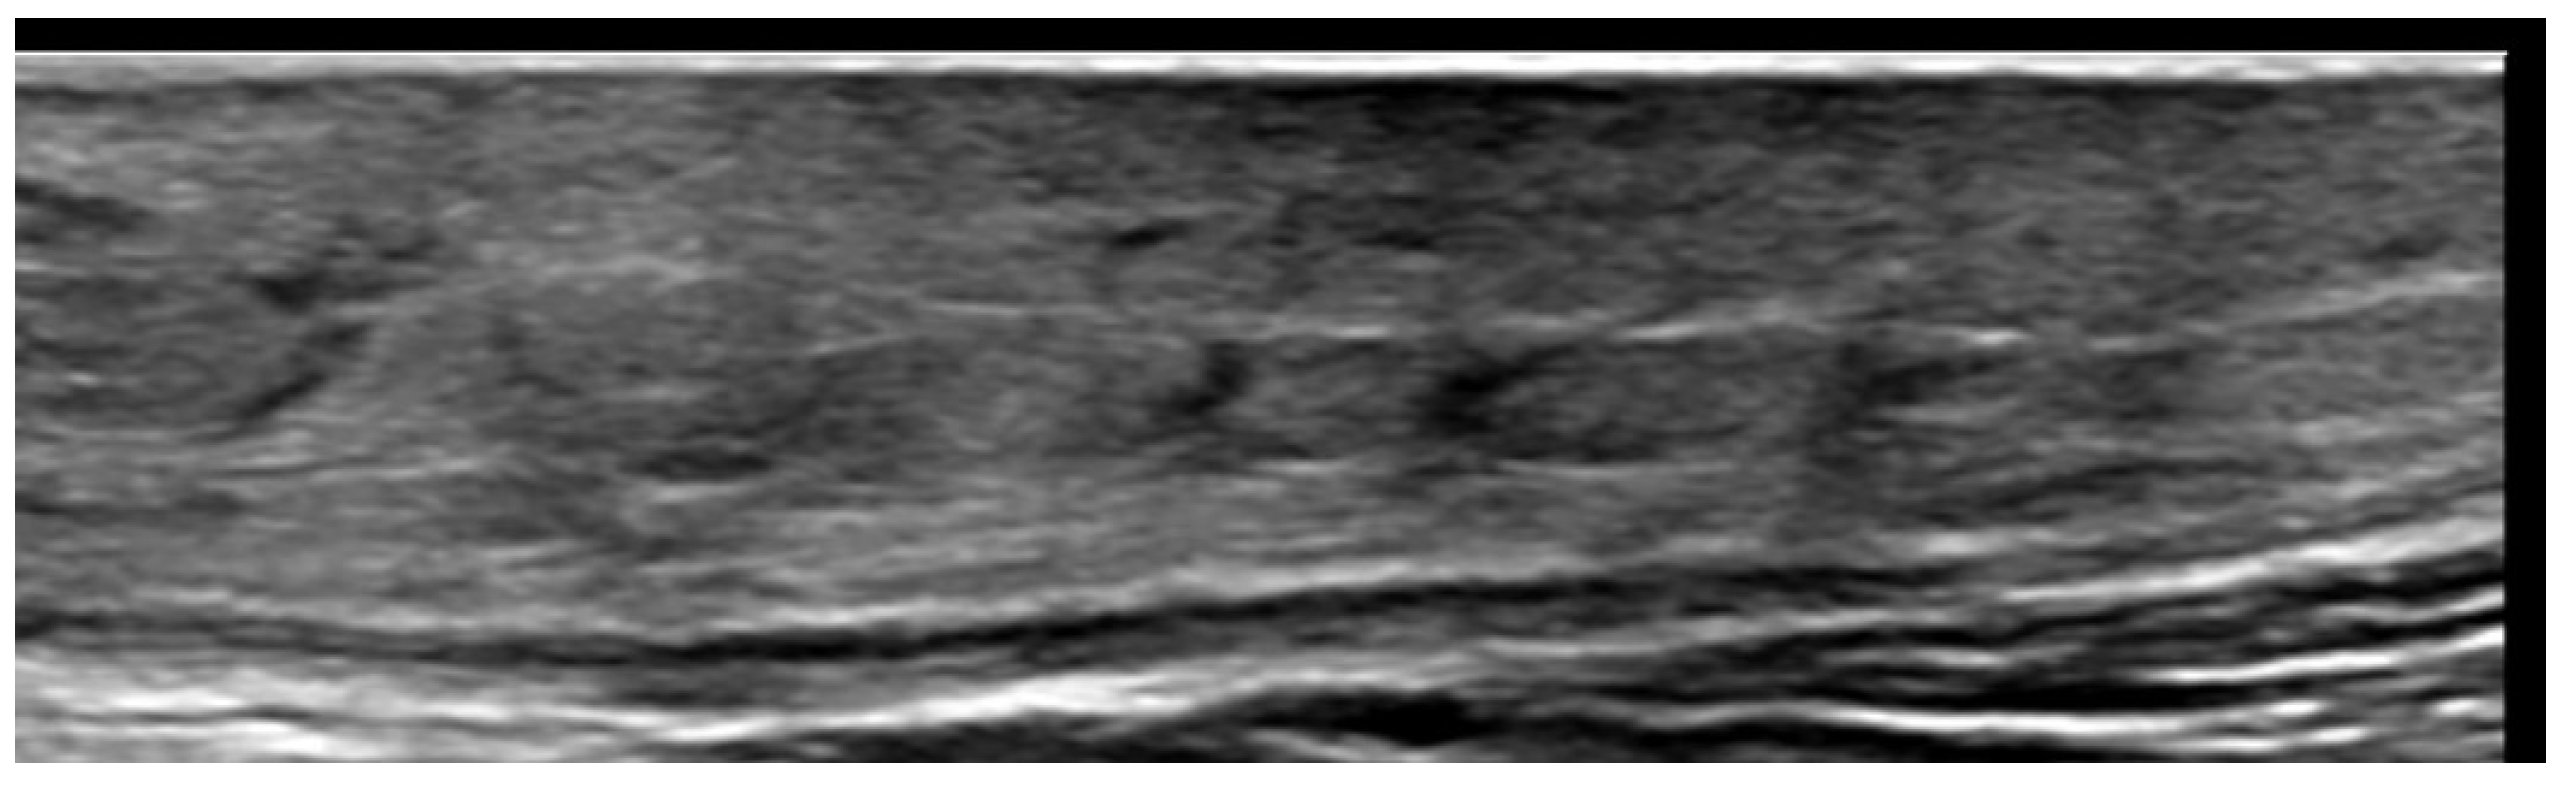

2. Infections

3. Inflammatory Dermatoses

4. Metabolic and Genetic Disorders

5. Specific Cutaneous Structure and Sites of Skin Disorders

6. Vascular Disorders

7. External-Agent-Associated Disorders

8. Neoplastic Diseases

9. Aesthetic Medicine